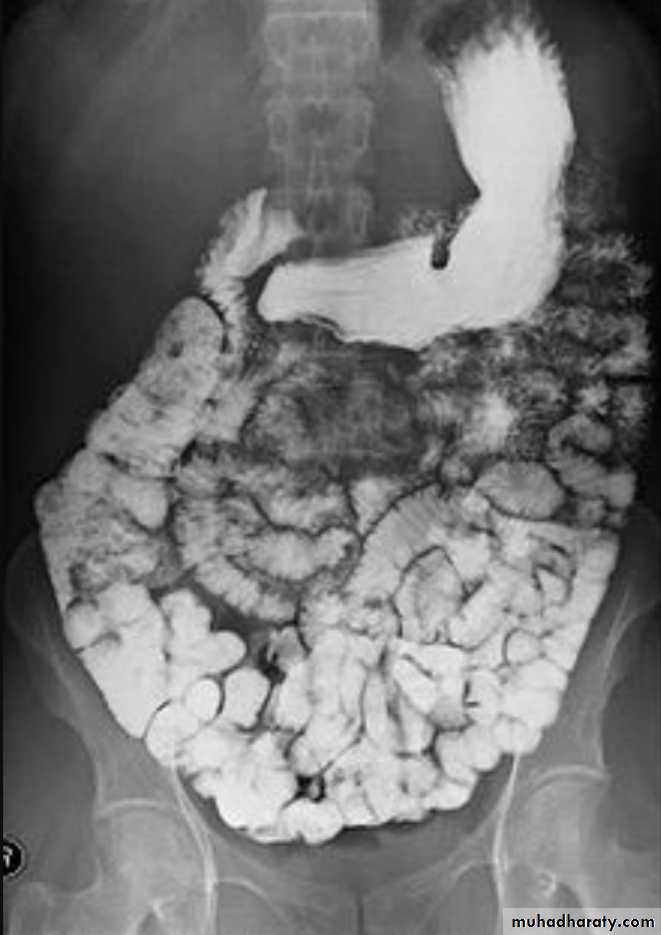

Ba examinationBarium studies of the small intestine Ba follow through Small bowel follow through (SBFT) routine investigation for delineation of all parts of the small boweldone with barium meal after having a quick look at esophagus, stomach, and duodenumRadiographic featuresOn a normal barium study of the small bowel, the jejunum is located in the upper left abdomen and the ileum in the lower right abdomen, to be continued by colon in ileo caecal region .The mucosa of the small bowel is characterized by the existence of the valvulae conniventes which give the small bowel normal feathery appearance in ba-follow through examination .

Barium small bowel follow-throughfindings of CD

Multiple mucosal ulcers aphthous ulcerslongitudinal fissures

Multiple skip lesions

when severe leads to cobblestone appearance

may lead to sinus tracts and fistulae

widely separated loops of bowel due to fibro-fatty proliferation

thickened folds due to edema

Pseudo diverticula formation: due to contraction at the site of ulcer with ballooning of the opposite site